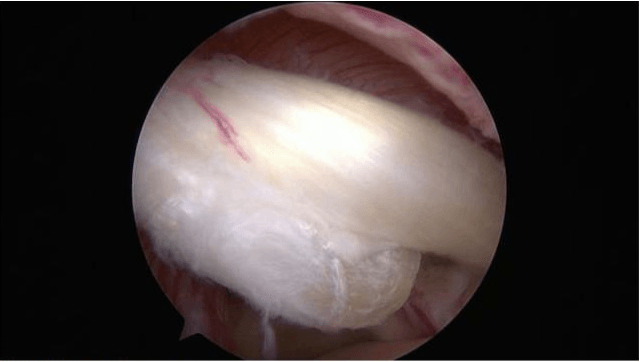

El tratamiento es esencialmente quirúrgico y varía en función del tipo de lesión:

- Bien una resección del rodete dañad

- Bien una reinserción del rodete

Es frecuente asociar a estos gestos sobre el rodete una tenotomía o tenodesis del tendón del bíceps largo (corte y fijación del tendón).

La cirugía se lleva a cabo por artroscopia y se puede realizar de forma ambulatoria.